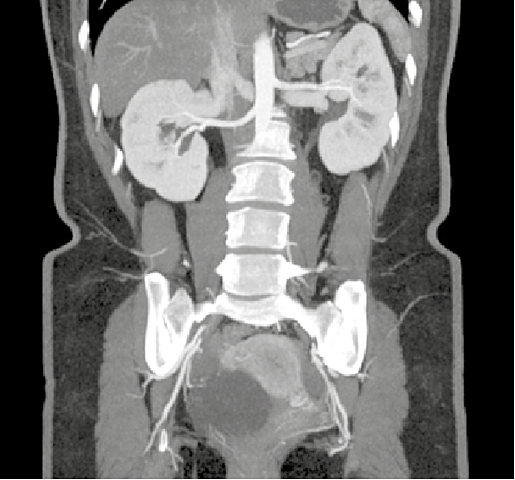

• Uso de yodo

Uso de yodo

Se empieza a administrar Yodo por via intravenosa en humanos para ayudar a resaltar vasos sanguineos, para mejorar la estructura tisular de de varios organos como cerebro, higado y riñones.